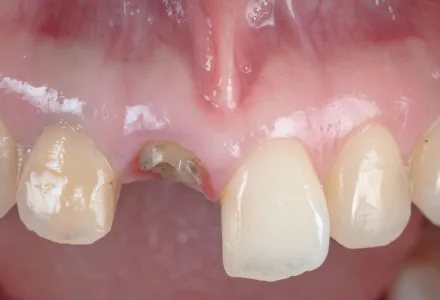

セラミック症例1

Before

After

- 治療名

- セラミックの詰め物

- 患者さん

- 30代 女性

- 執刀医

- 田中院長

- 治療

内容 - 今回は破折により形を失った右上前歯に対し、セラミックの詰め物を行いました。セラミックを被せることで見た目の自然さと機能性を回復しました。患者様から「前歯が欠けたときはとても落ち込みましたが、治療後は不安がなくなり、日常生活を明るく過ごせるようになりました。丁寧に治療してくださった田中院長に感謝しています。」とありがたいお言葉をいただきました。

- 治療期間

- 6ヶ月

- 治療費

- 800,000円〜

- リスク

- 強い力が加わると、割れたり欠けたりする可能性があります。